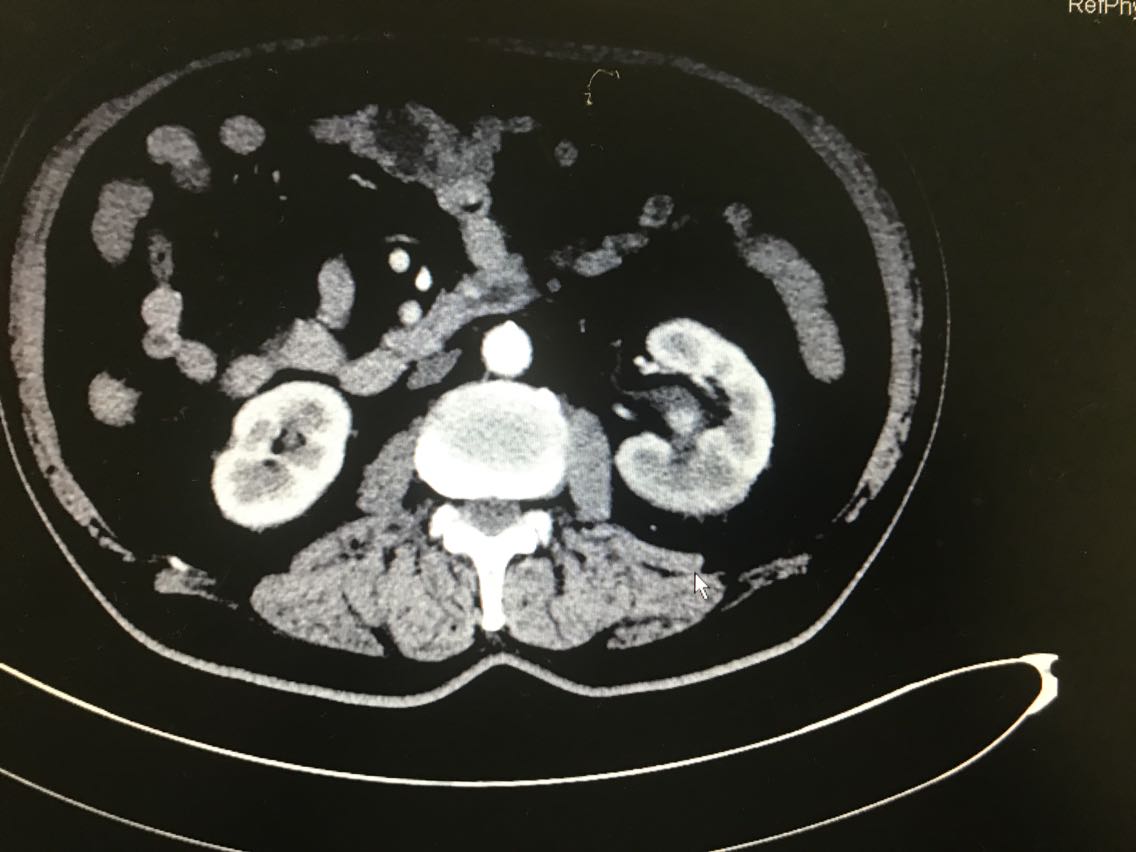

患者男性,81岁。 主诉:血尿伴左侧腰痛一月余 现病史:患者一月前出现血尿,伴左侧腰痛,于当地医院就诊,诊断为左侧肾盂占位。患者为求进一步治疗来我院门诊,门诊以肾盂恶性肿瘤收入院。起病以来,患者睡眠饮食尚可,二便无明显改变,体重未减。 既往史无特殊。

查体无特殊。 辅助检查: 全腹CT示:左肾上极肿块,侵犯左肾上盏并突入左肾盂,性质:左肾细胞癌可能性大,肾盂癌待排,结合临床。

诊断:左肾占位:肾盂癌? 治疗:腹腔镜左肾盂癌根治术